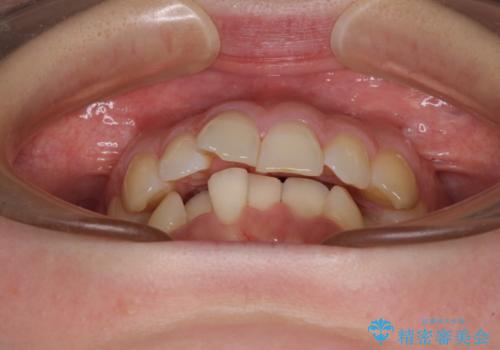

- 前歯のデコボコで前方に出ていることを気にして来院された患者様です。

上顎前歯が捻れて前方に飛び出しており、下顎前歯もそれに沿うようにデコボコとなっていました。

IPR(歯と歯の間を削る処置)によりスペースを獲得して上下顎前歯のデコボコを改善し、飛び出している前歯が引っ込むように設定し、インビザラインにて矯正治療を行うこととしました。